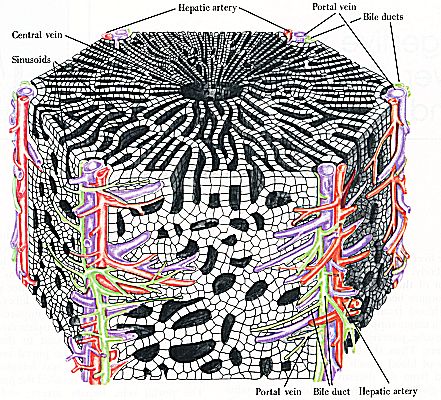

The histology of the liver is usually described on the basis of smaller units, called liver lobules. The most common description is that of the classic liver lobule, which consists of a number of liver cells (hepatocytes) surrounded by connective tissue. Such a liver lobule is usually hexagonal, with a central vein in the middle. The liver cells are arranged in plates with blood filled spaces, the sinusoids, in between the various plates of cells. At many of the corners of these hexagonal lobules, triads are found. Each consist of a bile duct, vein (branch of portal vein), and artery (branch of hepatic artery).

Fig RR472-01 Ross and Romrell p. 472 |